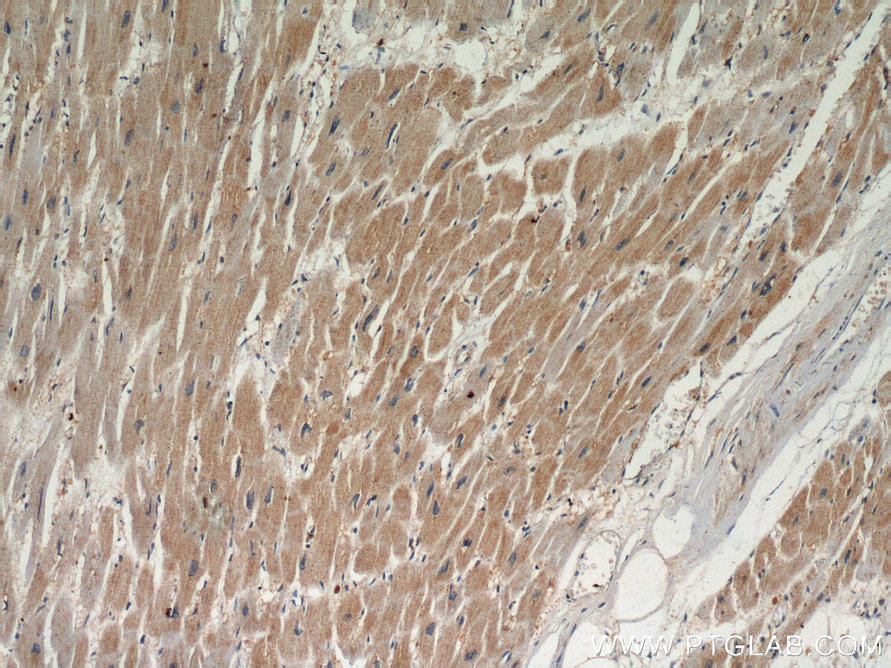

| Positive IHC detected in | human breast cancer tissue, human heart tissue, human skeletal muscle tissue, mouse heart tissue Note: suggested antigen retrieval with TE buffer pH 9.0; (*) Alternatively, antigen retrieval may be performed with citrate buffer pH 6.0 |

| Immunohistochemistry (IHC) | IHC : 1:50-1:500 |